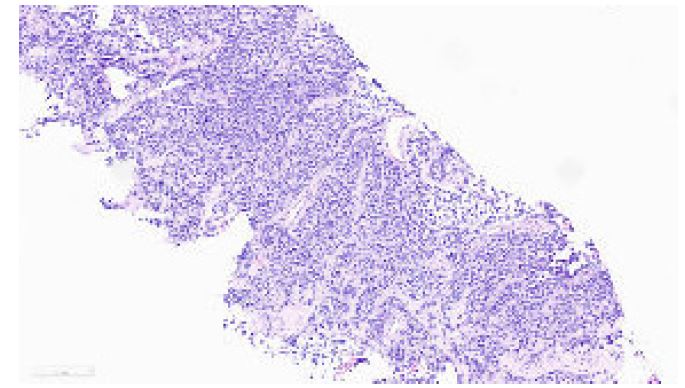

In January 2022, a 19-year-old pregnant female in her 36th week of pregnancy presented with a mass in the right forearm. The mass was investigated using Magnetic Resonance Imaging (MRI), the results of which are shown in Figures 1 and 2, revealing a suspicious lesion in the forearm flexor compartment. A subsequent biopsy was performed, and histopathological analysis confirmed the diagnosis of alveolar rhabdomyosarcoma as can be seen in Figure 3.

Figure 3: Core biopsy reveals cohesive nests of small cells exhibiting a high nuclear to cytoplasmic ratio and hyperchromatic nuclei. Notably, rhabdoid differentiation is observed a long side brisk mitotic activity.